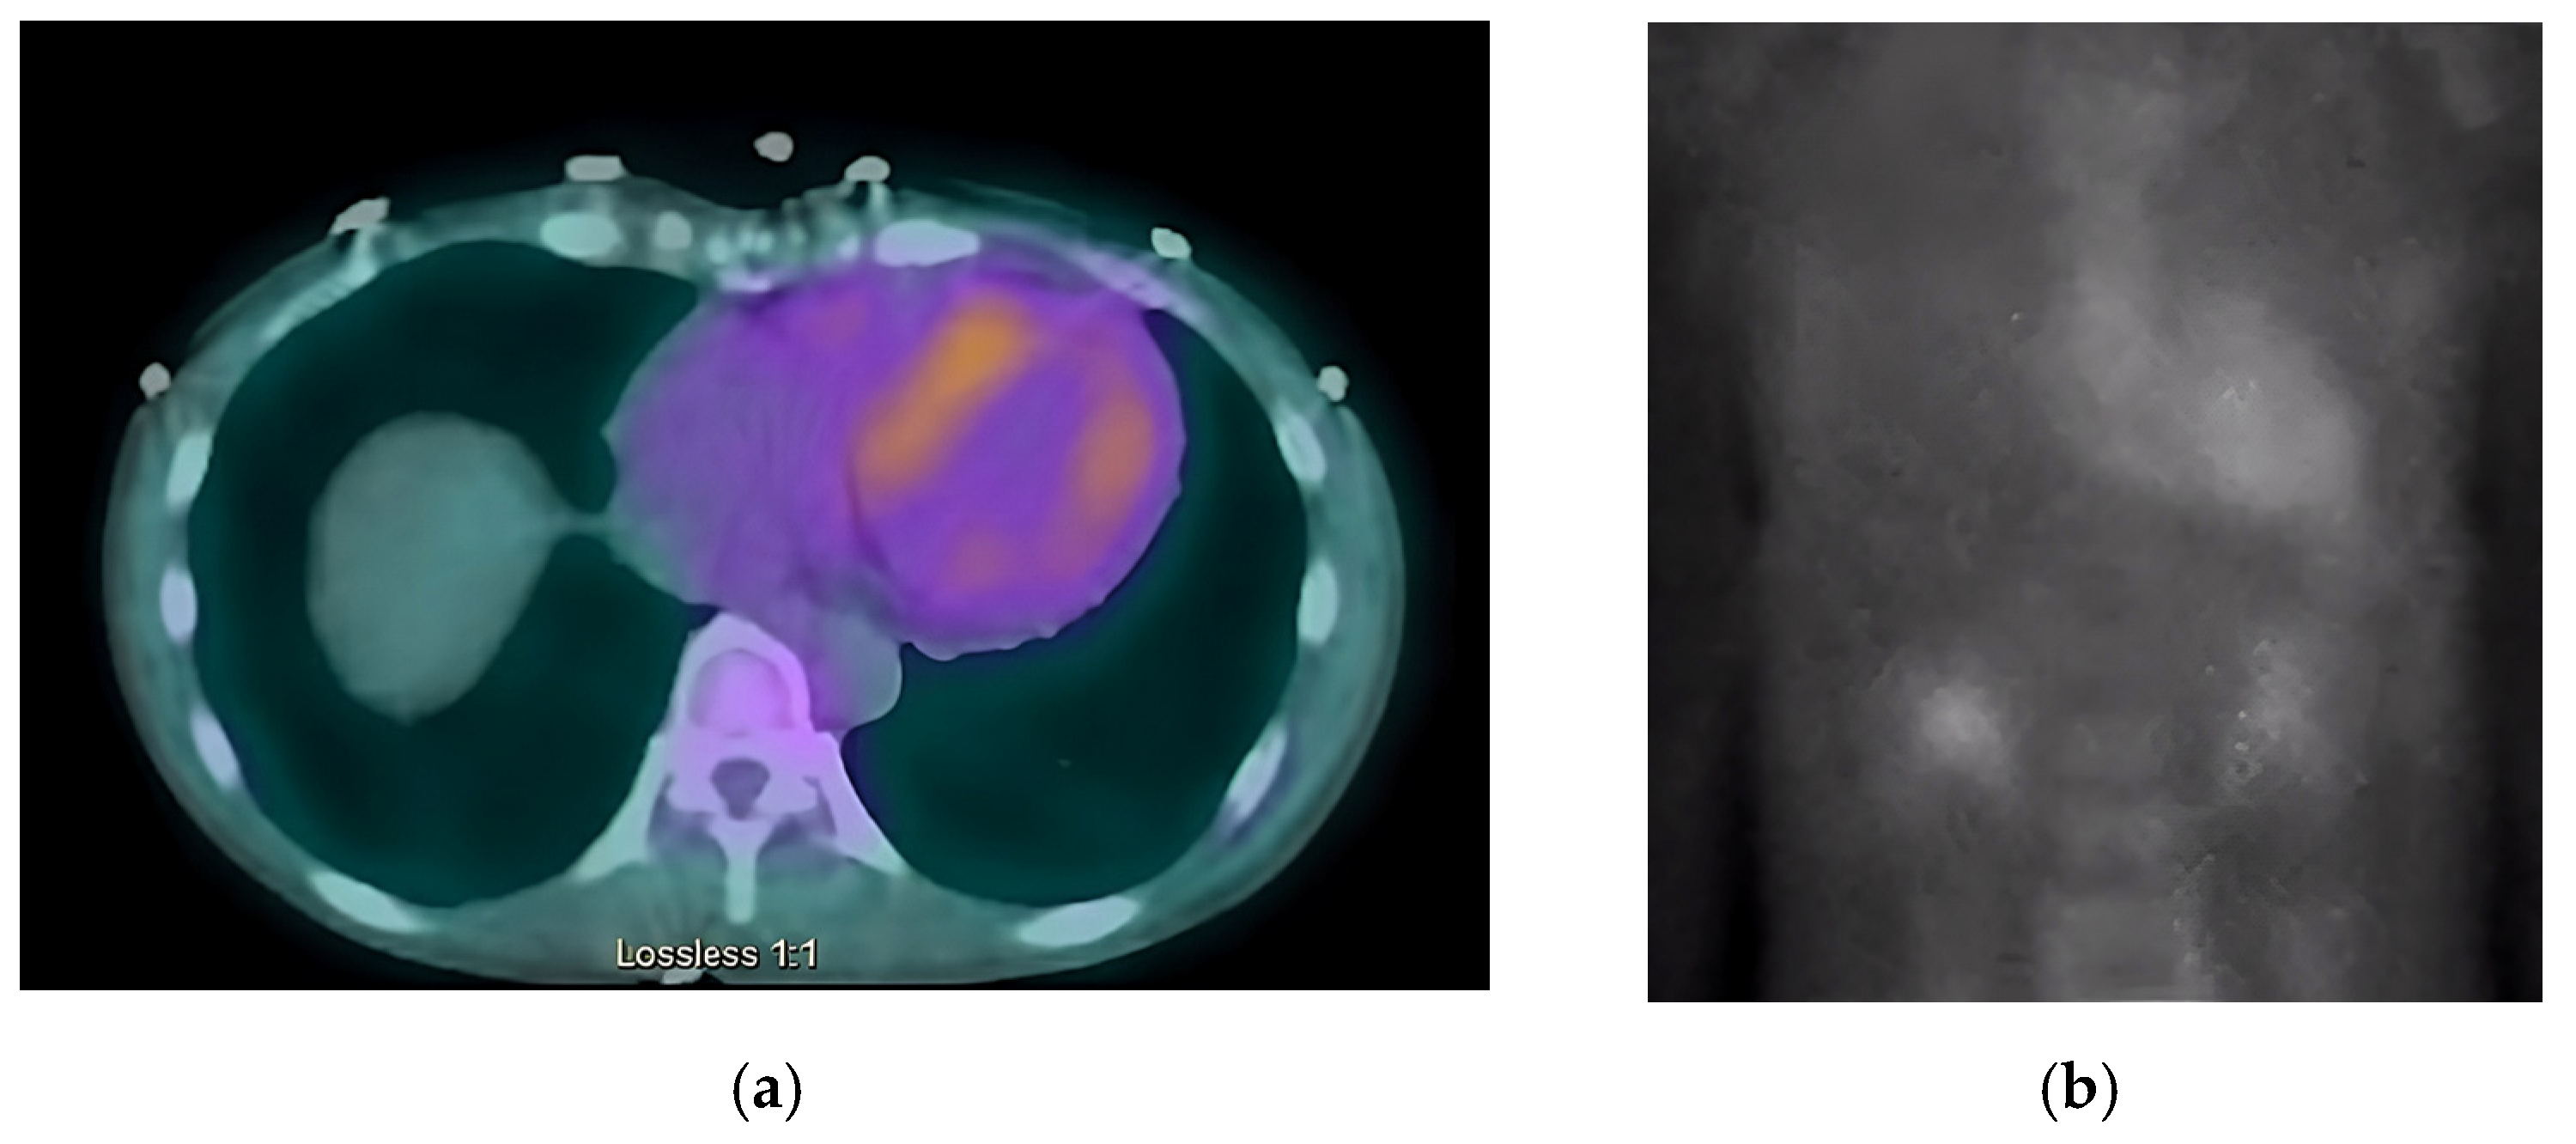

Next, we performed a 99Technetium pyrophosphate (99mTc-PYP) planar scintigraphy (Figure 4). A quantitative analysis of the heart retention pattern showed a heart-to-contralateral lung (H/Cl) ratio of 1.66 (Figure 5), strongly suggestive of amyloid deposition. To differentiate the type of cardiac amyloidosis, genetic testing was obtained and revealed a heterozygous pathogenic mutation in the TTR gene, diagnostic for TTR amyloidosis.

Radionuclide bone scintigraphy uses a bone-avid, phosphate-based isotope (99mTc-PYP) as a noninvasive way to diagnose ATTR. Phosphate-calcium binding seems to play an important role in the myocardial uptake of tracers, though the exact mechanism is unknown. Increased tracer accumulation in ATTR may suggest it has a higher calcium level than AL, and/or the duration of amyloid deposition increases uptake as ATTR has a more indolent course. Scoring cardiac uptake of the tracer is done via a semi-quantitative method using the Perugini grading scale (graded from 0–3). It visually compares tracer uptake in the myocardium and ribs of the planar image. 99mTc-PYP with abnormal uptake (grade 2 or 3) in the absence of a monoclonal gammopathy has a specificity and positive predictive value of 100% for diagnosing ATTR-CA. However, genotyping is still required to differentiate hATTR and wtATTR. If hATTR is present, first-degree relatives should be tested for the identified variant [25]. A heart-to-contralateral lung ratio > 1.5 has a 97% sensitivity and 100% specificity in differentiating ATTR from AL [28]. In patients with a monoclonal gammopathy, scintigraphy alone cannot be used to diagnose ATTR, and an endomyocardial biopsy (EMB) is required for diagnosis. Currently, imaging techniques allow for an accurate and noninvasive method to diagnose ATTR without the need for confirmatory myocardial biopsy. However, if you need to differentiate ATTR with concomitant MGUS from AL, an EMB is indicated. Lastly, a plasma cell dyscrasia with equivocal cardiac imaging findings is another indication for EMB [28].

Figure 4. SPECT in an ATTR cardiac amyloidosis patient. Evidence of uptake of 99mTc-PYP in the myocardium. (a) Quantitative SPECT/CT; (b) Semiquantitative analysis of 99mTc-PYP myocardial uptake.